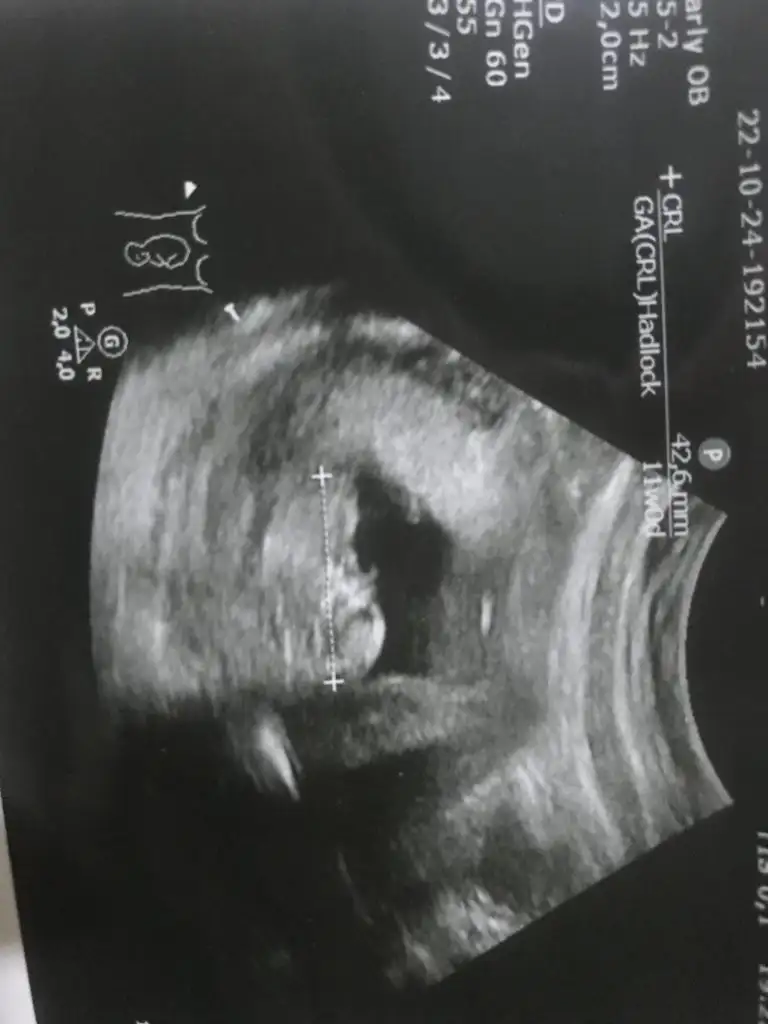

5 ve 14. haftaya kadar olan ultrason fotolarınızı paylaşın. Vajinadan mı yoksa karından mı çekildiğini ve kaç haftalık olduğunu da mutlaka belirtin.